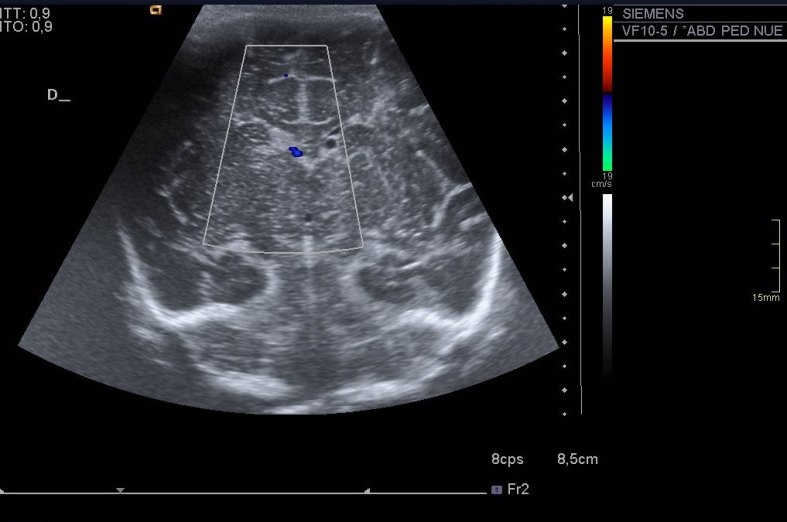

293. Hemorragia Matriz Germinal Grado 1.

Uno de los lugares más especiales para hacer ecografía es en los servicios de neonatología. Hacer una ecografía transfontanelar a un recién nacido es una experiencia inolvidable, es de las pruebas a las que uno le pone siempre especial cariño. Particularmente a mi, me superencanta. Hoy quería subir este caso, muy sencillo. Muy bonito. Me acuerdo de ella, era muy linda.

En el caso de esta pequeña nos pidieron una ecografía de control de una hemorragia de la matriz germinal grado 1 diagnosticada a las pocas horas de nacer.

La hemorragia es la imagen hiperecogénica, homogénea y psudoredondeada del lado derecho. El quiste, redondo e hipoecogénico, del lado izquierdo. No se pudo demostrar una hemorragia en ese lugar.

Pequeña hemorragia matriz germinal lado derecho, grado uno, y pequeño quiste asociado izquierdo indicando reabsorción parcial en ese lugar. Imagen 1.Sistema ventricular de tamaño normal. Imagen 1 a 4.

El índice de resistencia vascular se encontraba en los márgenes normales. Imagen 5.